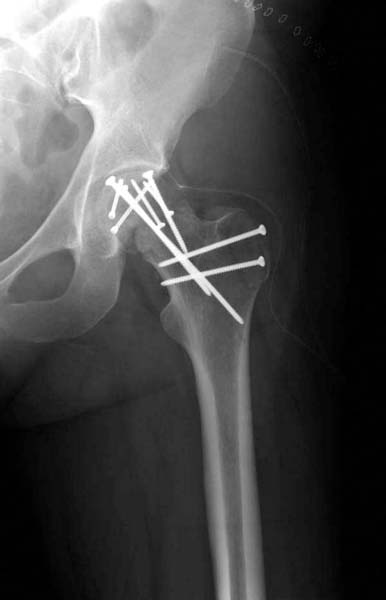

> Больная стабильная после хирургических мероприятии и получив добро,

> приступили к закрытому вправлению таранной кости с укладкой наружного

> фиксатора. Затем укладка больную на бок и открытый остеосинтез

> перелома-вывиха головки бедра.

> По характеру повреждения головка находится сзади и напрашивается задний

> Кохер-Лангенбек доступ, но в заднем доступе имеется риск повреждения

> магистрального кровоснабжения головки a. circumflexa. Более щадящая

> trochanteric flip (digastric osteotomy) сохранит кровоснабжение и дасть

> возможность работу при вывихнутом суставе.